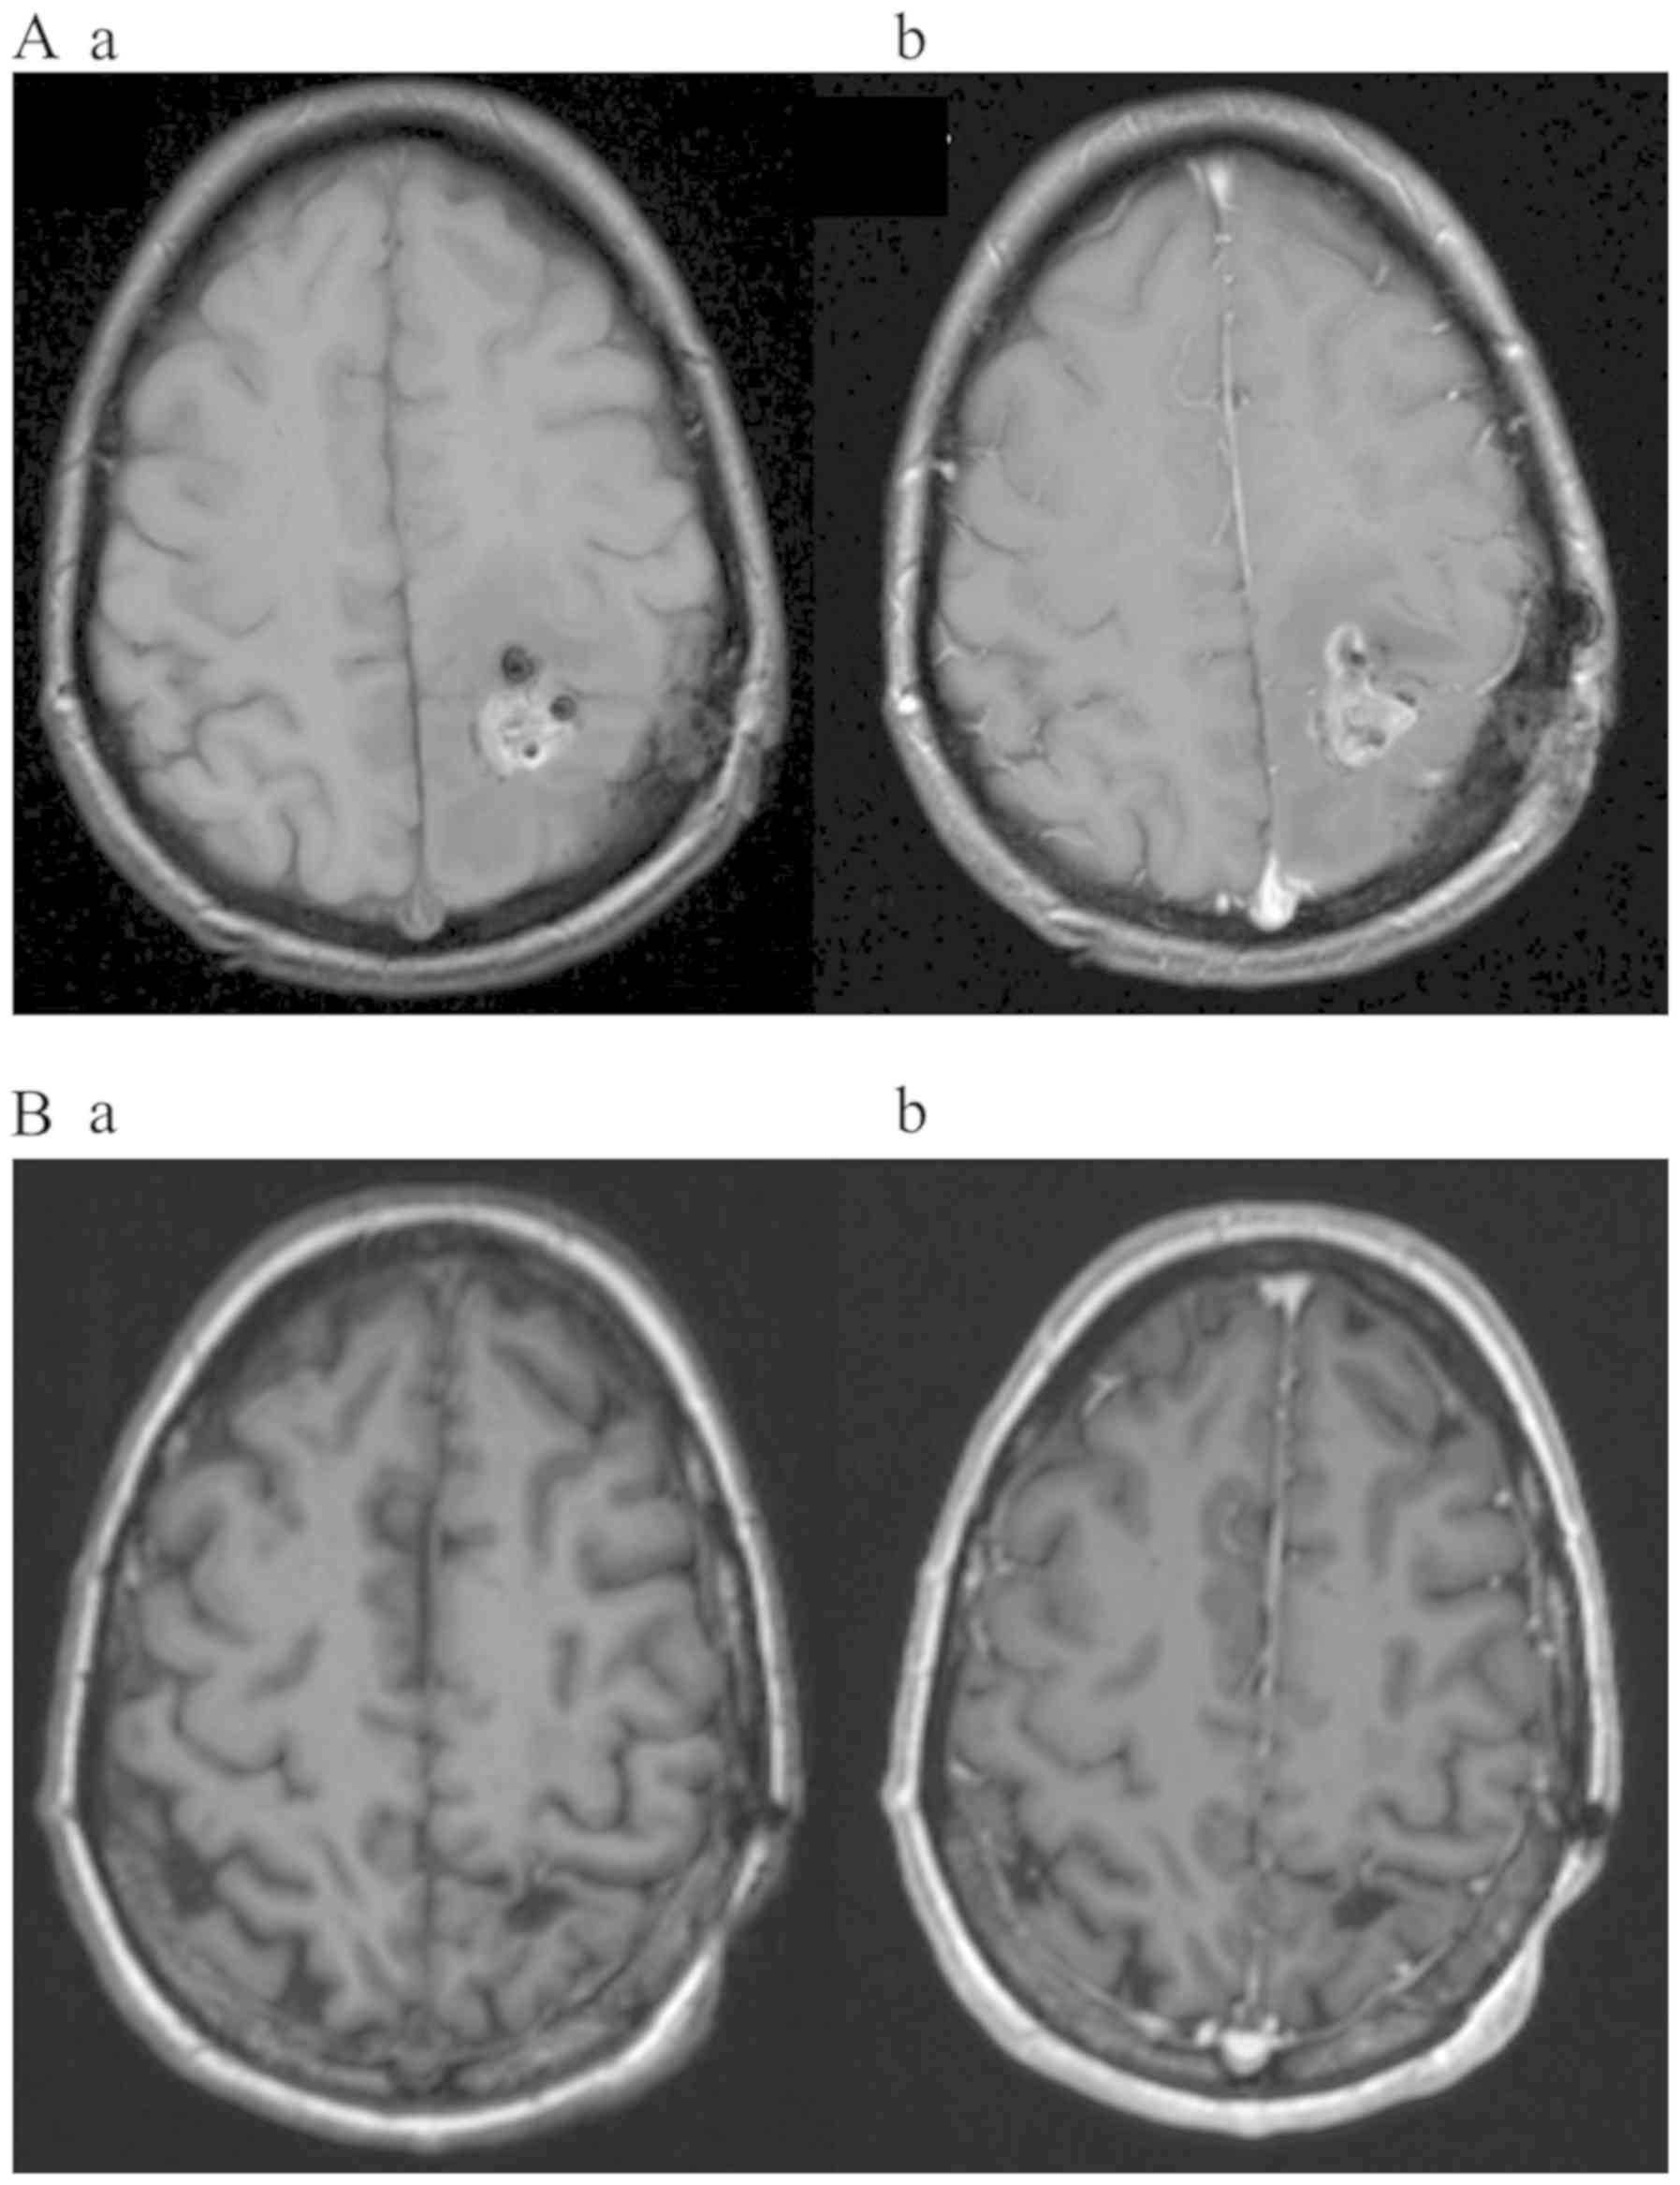

Patient one (female, 54 years, KPS 80%) presented with recurrent speech impairment. A CT scan revealed a left frontotemporal lesion with perifocal edema. MRI revealed an irregular contrast enhancing tumor highly susceptible for GBM, located in the frontal operculum and in close contact to the caudate nucleus and anterior crus of the internal capsule with moderate compression of the lateral ventricle and midline shift. After 5-ALA- and ultrasound-guided resection, the early postoperative MRI showed remaining tumor tissue in the rostral and dorsolateral marginal zones of the resection cavity, confirming a STR (Fig. 1A). Apart from a slight dysphasia, no neurological abnormalities were recorded after surgery. The histological diagnosis confirmed GBM WHO Grade IV, with methylated MGMT promoter, IDH1/2 wild-type and sustained nuclear expression of ATRX. Concomitant radiochemotherapy was administered (53.4 Gy/Temozolomide (TMZ) with 75 mg/m2 daily). A follow-up MRI at 3 months postoperatively and at 2 weeks after radiation termination showed a new contrast enhancement at the rostral margin of the left ventricle in an area initially suspected as non-contrast enhancing tumor. This new contrast enhancement was interpreted as pseudoprogression, while the postoperative residual tumor was defined as stable. The adjuvant chemotherapy with TMZ according to the Stupp protocol (10) was initiated 4 weeks after termination of radiochemotherapy. Application of TTFields was started at the same time. The patient was in a good general condition during the first cycle of TMZ, but suffered from persisting speech impairment. Due to leukocytopenia, the third cycle of TMZ was delayed for a month while TTFields therapy was applied continuously. Speech impairment improved, and the next follow-up MRI 4 months after surgery indicated reduced contrast enhancement of the pseudoprogression as well as the residual tumor. After termination of 6 cycles of TMZ, the patient continued with TTFields treatment at a median compliance rate of 92% [range: 88–96%]. The MRI at five months after TTFields start did not show any contrast enhancement indicating a CR according to the RANO criteria (9) in both regions, residual tumor and pseudoprogression as well. The patient's status remained stable for 7 months (Fig. 1B) before multifocal tumor recurrence occurred. Since resection was not feasible, the patient was treated with re-irradiation and further 6 cycles of TMZ. TTFields was discontinued due to patient's decision at 12 months after initiation for 23 days. Afterwards, the patient resumed TTFields treatment, which is still ongoing for 24 months in total. The patient presents a mild decline of neurological functions due to slow but ongoing tumor growth.

Figure 1.

Axial T1-weighted MRI [native (Aa/Ab)] and contrast enhanced (Ba/Bb) images of patient one (female; 54 years old). (A) Incomplete resection was exhibited at 24 h post-surgery. (B) Complete radiological response according to rapid assessment in neuro-oncology criteria under dual therapy with TMZ and TTFields was demonstrated at 14 months. Arrows indicate residual contrast-enhancing tumor after STR. TMZ, Temozolomide; TTFields, Tumor Treating Fields.